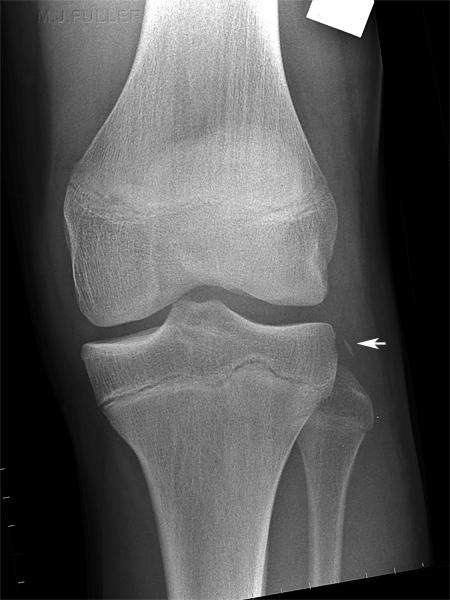

Segond Fracture

This is a very subtle "avulsion fracture of the tibia below the articular margin" caused by traction on the capsular or coronary ligaments. It is not possible to cause this fracture without first rupturing at least one of the major ligaments in the knee.

The classical description1 is limited to the lateral side where associated injuries include:-

Examples in order of increasing subtlety: -